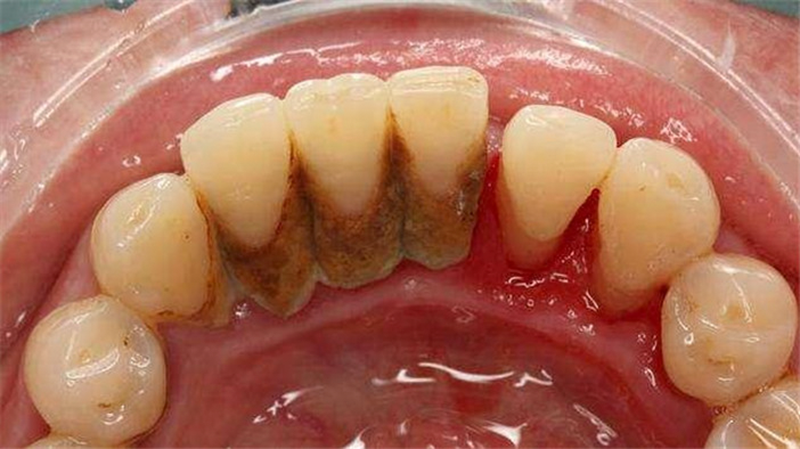

Bạn đã biết cạo vôi răng là gì rồi, vậy vì sao cần phải cạo vôi răng đúng quy trình? Các mảng bám tồn tại xung quanh răng gây kích ứng mô nướu, dẫn đến nhiều bệnh lý về răng miệng như sâu răng, viêm nha chu, viêm lợi, chảy máu chân răng,... Hay nghiêm trọng hơn còn làm răng lung lay, mất răng sớm, tiêu xương hàm.

Vôi răng không chỉ xuất hiện trên thân răng mà chúng còn bám lại ở đường viền nướu. Vậy nên, muốn đạt hiệu quả cao khi cạo vôi răng bạn phải lựa chọn địa chỉ nha khoa uy tín, nơi có bác sĩ giỏi thực hiện dựa trên sự hỗ trợ của máy móc thiết bị hiện đại. Hạn chế xảy ra sai sót, đảm bảo an toàn trong suốt quá trình lấy cao răng.

Sau khi cạo hết vôi răng trên thân răng, bác sĩ sẽ tiếp tục loại bỏ mảng bám trong kẽ răng và khu vực răng với nướu. Vôi răng bám lại tại đây chính là nguyên nhân gây ra các bệnh lý như viêm nha chu, viêm nướu. Lấy cao răng ở vị trí này khó khăn hơn, bác sĩ cần nạo sâu xuống mới làm sạch hết được, tốn nhiều thời gian và phải làm thật tỉ mỉ để không gây chảy máu.